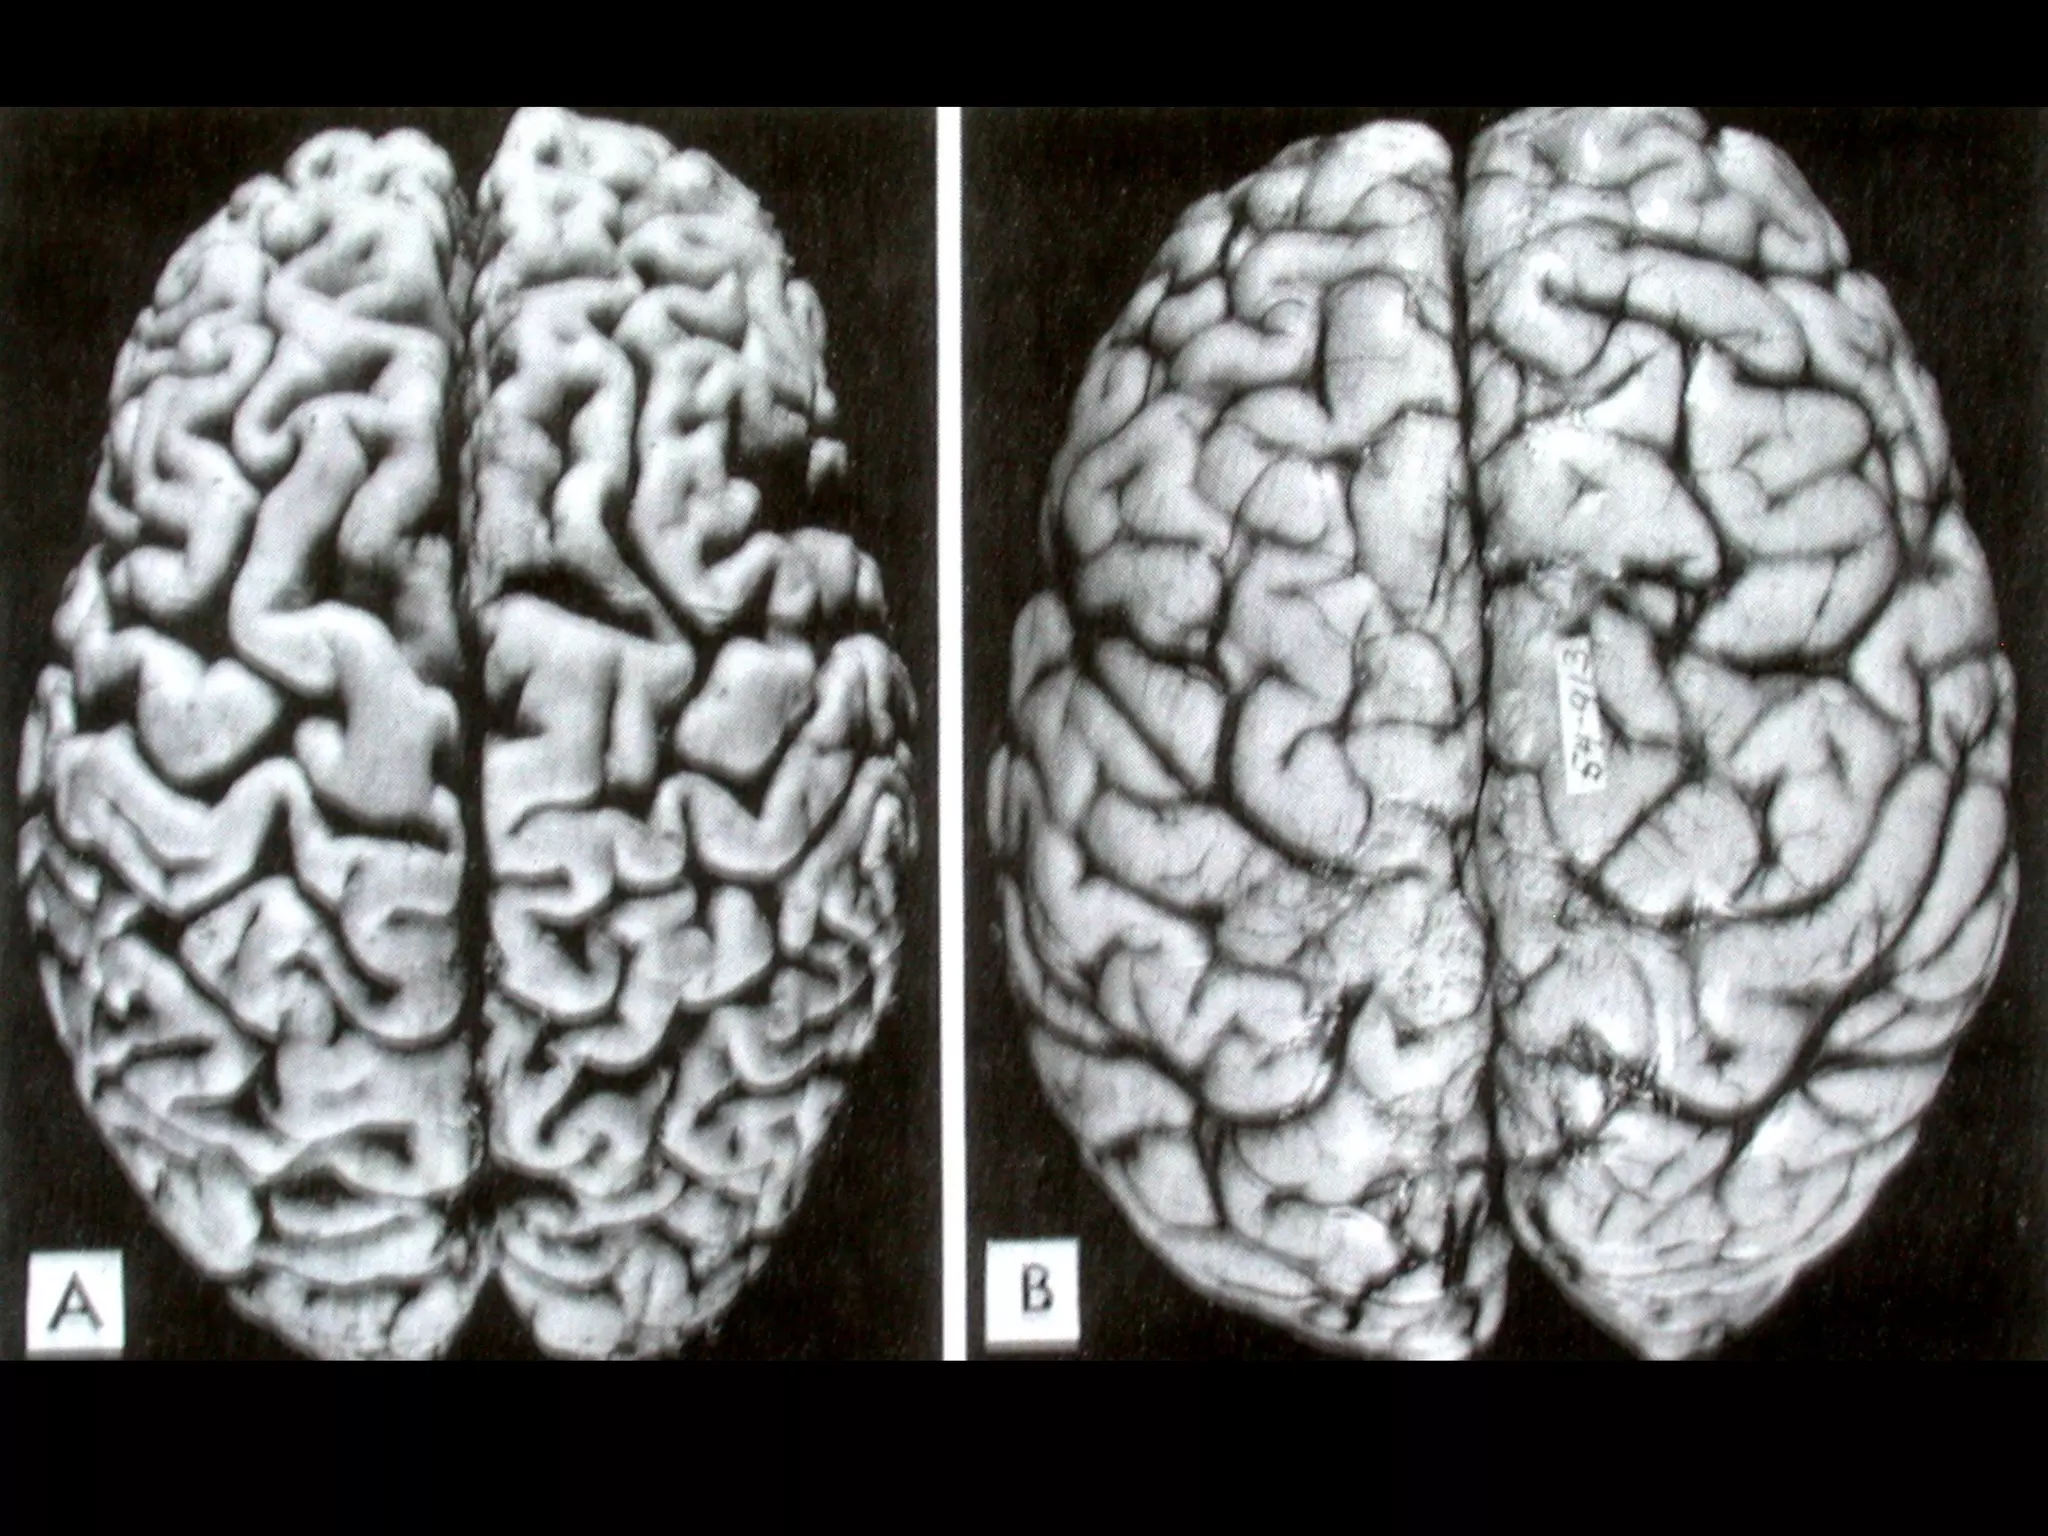

• #33 The testis at the right has undergone atrophy and is much smaller than the normal testis at the left.

• #35 FIGURE 1-33  Lipofuscin granules in a cardiac myocyte shown by (A) light microscopy (deposits indicated by arrows), and (B) electron microscopy (note the perinuclear, intralysosomal location).